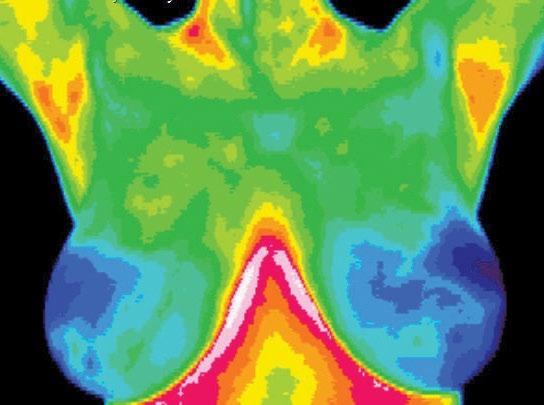

Total Breast Health

Women are encouraged to get a mammogram so they can find any presence of breast cancer as early as possible. But instead of early detection, let’s be proactive in our breast health and identify risk factors so plans can be put into action to improve the health of the breast and reverse develop ing pathology. This is preven tion—not just early detection.

Mammograms image the structure of the breast and thermography images the physiology (for example, an x-ray of your heart shows how big it is and where it is in your chest, whereas an EKG will show the function of the heart). Thermography “shows” the function of the breasts and how healthy they are. Mammograms are after the fact; they can only see what is already there. They can identify a mass, if it is large enough, but cannot distinguish the difference between a benign lump and a a possible cancerous tumor. A tumor must be fed by blood vessels, and that vascular formation starts many years before the tumor begins to grow. The vascular feed produces heat which can be seen with thermal imaging. This is an indication that either the body is preparing to produce a possible cancerous tumor or the mass that is present could possibly be cancerous.

There is a large margin between healthy breasts and breast cancer, and it’s helpful to know where you fall within that spectrum. There are many factors that can contribute to unhealthy breasts, such as dense and fibrocystic breasts, calcifica tions, lymph congestion, inflamma tion, thyroid dysfunction, hormone imbalances and more, which can contribute to dis-ease and a pos sible unfavorable diagnosis down the road.

Thermography can tell you how healthy the breasts are instead of just screening for breast cancer. It also has the potential to truly detect breast cell anomalies long before mammography can detect can cer. This allows one to implement lifestyle changes that can improve the health of the breasts proactively instead of waiting for a cancer diag nosis later.

It is important to know what’s hap pening so you can make positive

changes to improve your breast health. Thermography is an excel lent tool for you and your healthcare practitioner to help identify specific challenges and then monitor the results of the changes you make.

There are many things that we can do to avoid breast cancer, but knowing our risk factors should be at the top of the list. With proper risk assessment that includes different testing modalities, a client is able to determine their risk factors and develop an action plan on how to improve the breast tissue or even reverse the existing developments. Or hopefully, see that you have a low risk for breast cancer so you have one less thing to worry about. Knowledge is power.

Lisa Holliday is a Clinical Thermographer at Inflam mation Imaging of Tucson. Connect at 520-468-1530 or InflammationImaging.com. See ad, page 25.